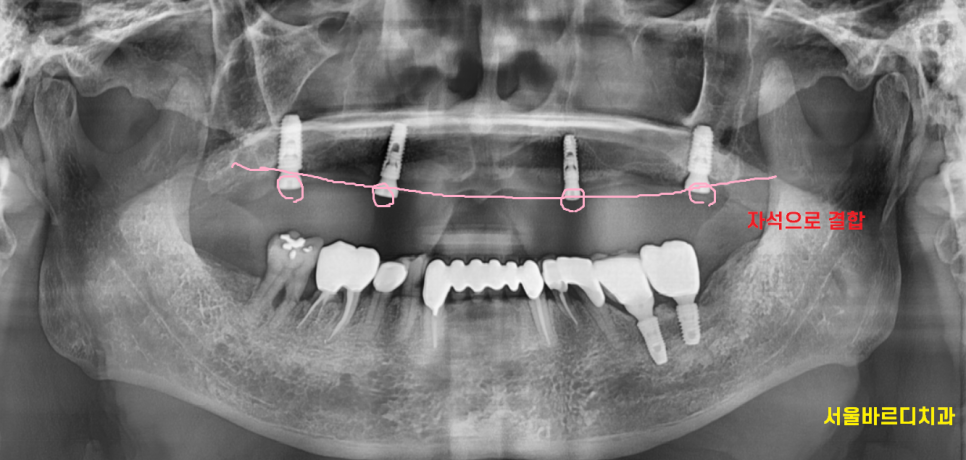

오버 덴쳐란 무엇이냐?

전체 치아 상실 시

부분적으로 임플란트를 심는겁니다.

보통 2-4개의 임플란트를 심는데

환자분의 잇몸 상태에 따라 달라지게 됩니다.

그리고 임플란트 위에 자석을 연결하여

틀니를 붙이게 되는데요.

그래서 자석 틀니라고 불립니다.

틀니를 기존에 잇몸 위에 얹어서 사용했다면

임플란트와 결합하여 사용하는것이죠.

엑스레이를 찍어보면

임플란트가 심어져 있답니다.

임플란트와 틀니를 자석으로 연결하니

접착력이 좋다

잘 안떨어진다~~~